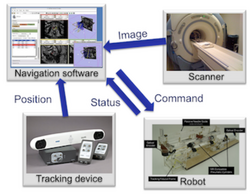

Slicer4 IGT

- Slicer IGT tutorials

- Authors: Tamas Ungi, M.D, Ph.D., Junichi Tokuda, Ph.D.

- Audience: End-users interested in using Slicer for real-time navigated procedures. E.g. navigated needle insertions or other minimally invasive medical procedures.

- Modules: SlicerIGT Extension

- Based on: Slicer4.3.1-2014.09.14

- Data: Slicer-IGT datasets